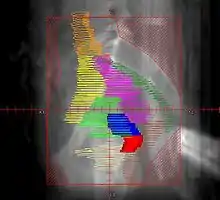

Example of a lateral radiation therapy treatment field for Stage IB2+ Cervix used at Tufts/Brown residency program. Actual patient contours should guide field design and AP/PA vs. 4F decision.